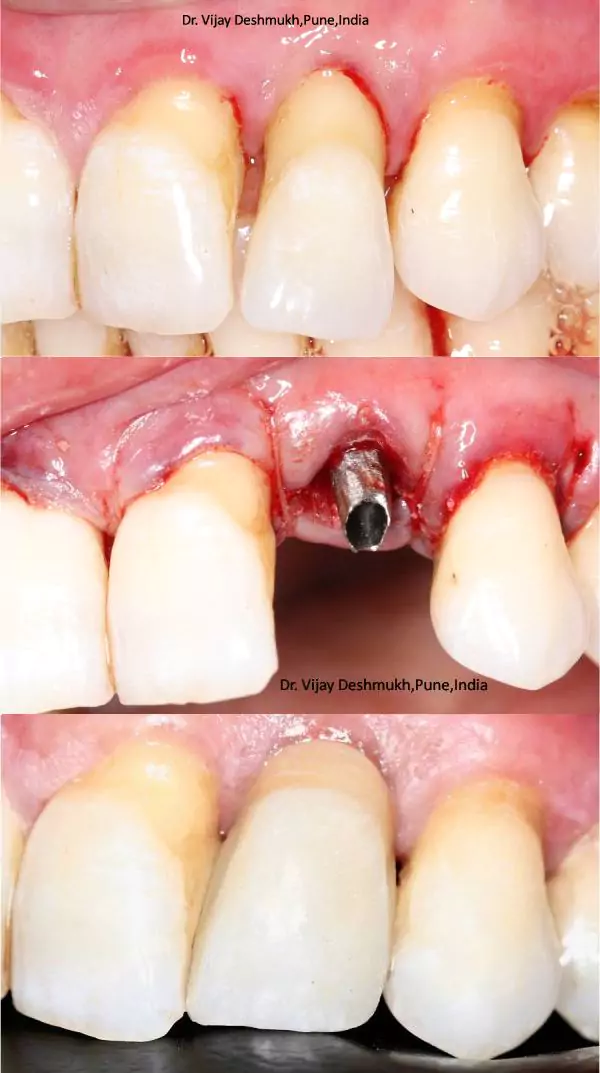

Before & After Transformations

Smile Gallery

Smile Journey Highlights